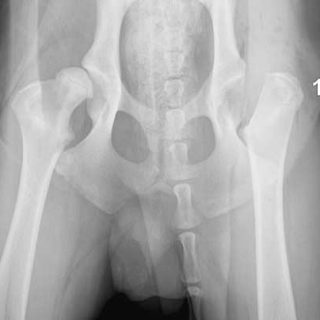

Cuidado: Puedes estar provocando displasia a tu cachorro

Un porcentaje importante de las displasias (de codo y cadera) se pueden evitar. Tienen mucho que ver las circunstancias ambientales, te detallamos las dos más importantes.